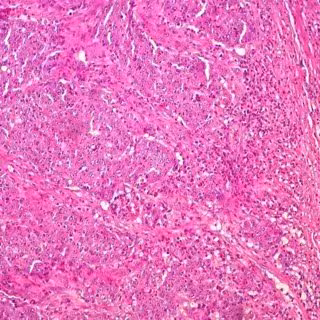

Hallan un nuevo culpable del cáncer de colon en el microbioma intestinal

Cáncer de colon

Foto: UCM